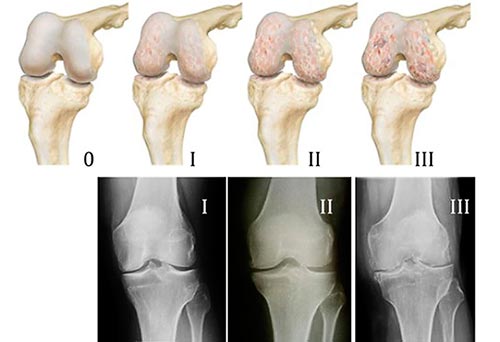

ДОА коленных суставов имеет 3 степени.

При 1 степени боль ощущается только при движении. В покое она сразу проходит. В суставной полости скапливается небольшое количество жидкости. Хрящи уже претерпевают изменения, однако внешне это никак не проявляется.

Гонартроз(остеоартрит коленного сустава) 2 степени: рентгеновский снимок покажет разрастание костной ткани. Во время любых движений чувствуется сильная боль. Она не прекращается даже в состоянии покоя. Отчетливо слышен хруст. Колени теряют свою функциональность. При внешнем осмотре врач видит деформацию.

Остеоартроз колена3 степени:хрящи настолько истончены, что обнажают кость. В пораженных участках откладываются соли, что приводит к появлению остеофитов. Деформированное соединение постоянно болит. При диагнозе артроз колена симптомы и лечение усложняется и боли выражены максимально сильно.

Все степени артроза коленного сустава имеют свои признаки и, как следствие, способы лечения.

Что такое артроз, как он проявляется в коленном суставе, также как и распознать стадии артроза коленного сустава поможет лечащий вас врач и рентген. Наиболее эффективным он является на поздних этапах развития болезни. Снимок покажет размер суставной щели, состояние хряща, повреждения костной ткани и количество солей.